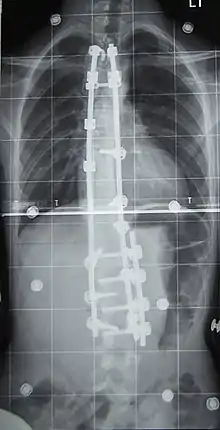

والعمل الجراحي يقوم على وضع جهاز مفصلي من المعدن بالإضافة إلى أحد اضلع المريض الذي يقطع إلى قطع تساعد ياضافتها إلى الجهاز بتقويم الفقرات وتخفف من حدة انحناء العمود الفقري ولكن بدرجة معينة. كما نرى في الصورة جانبا.